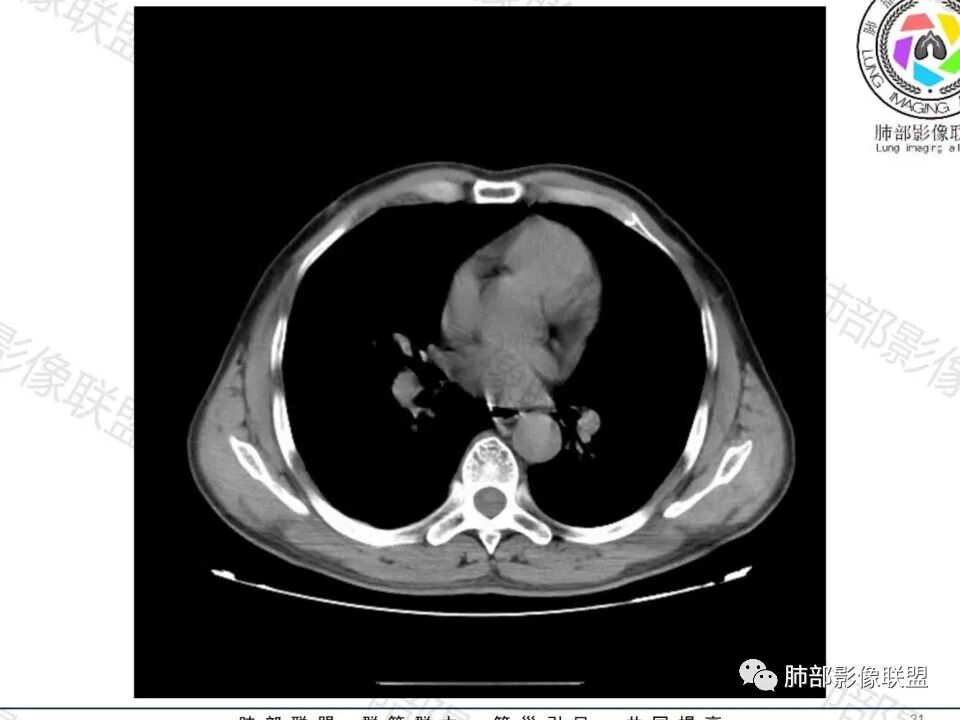

大家目前碰到多数结节是磨玻璃结节,对于实性结节的诊断反而陌生,其实性结节才是考验脑子的时候;

这枚结节的纵隔窗在没有调节窗位的情况下,已经很密实了,说明这个结节里面是软组织的成分,这与普通炎性结节(隐球菌等)的密度还是有区别的,很多年前就有人提出,纵隔窗显示越大,恶性可能越大;

结节周围有磨玻璃影,边界似清不清的,但是总体不如炎性晕征那么模糊;

增强的程度很难讲,但是不均匀强化是可以确定的;

有收缩力,但是很轻,按照常理,实性结节因为有占位效应,不太会有收缩力,但是叶间胸膜有凹陷。所以讲,这个结节还是开了放心。